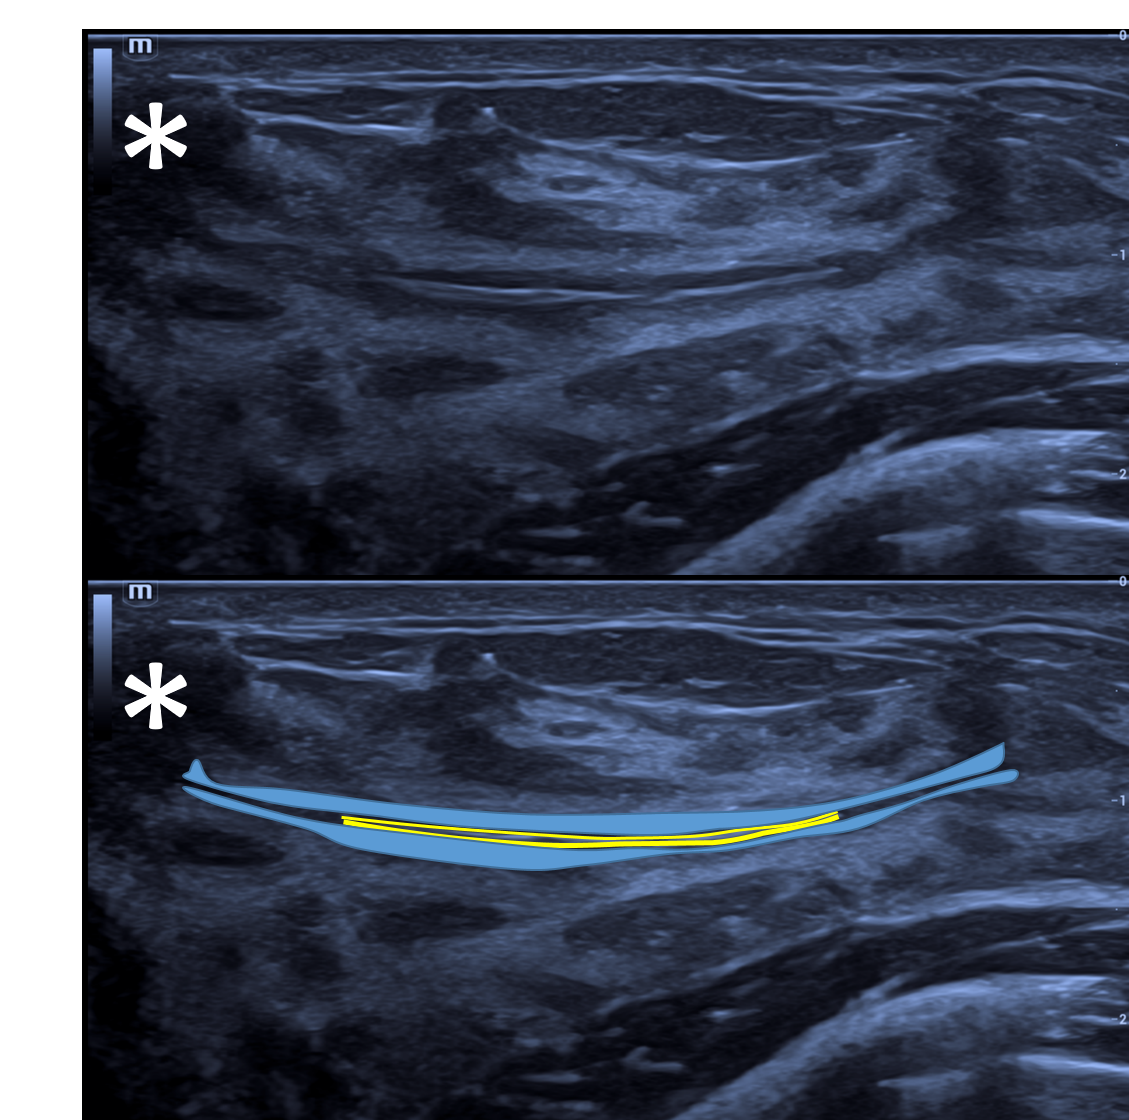

Os ductos mamários apresentam-se à ultrassonografia como estruturas lineares hipoecoicas a isoecoicas, com disposição radial a partir da papila, semelhante aos raios de uma roda. Próximo à papila, seguem um trajeto mais vertical (ântero-posterior), tornando-se progressivamente mais horizontais à medida que se afastam.

O aspecto sonográfico dos ductos é altamente variável e depende principalmente da quantidade de estroma periductal frouxo fibroelástico, do grau de distensão luminal por secreções e da ecogenicidade desse conteúdo. Esse estroma periductal, relativamente isoecoico, pode aumentar o tamanho aparente do ducto, fazendo com que pareça maior do que seu lúmen real.

Em condições ideais, a parede ductal pode ser identificada como uma linha ecogênica fina em cortes longitudinais e como um eco central circular ou linear nos cortes transversais, especialmente na ausência de ectasia ductal.